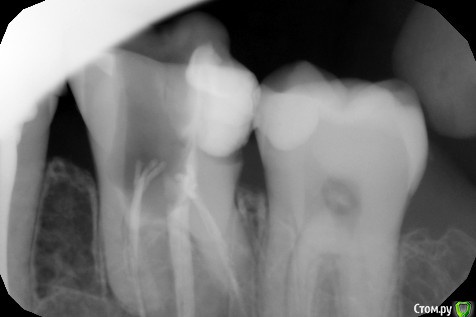

ЛолаN Опубликовано 29 мая, 2018 Поделиться Опубликовано 29 мая, 2018 Добрый день.2 недели назад стал беспокоить зуб.На осмотре стоматолог предложил его удалить. Так как удалять не хотелось, решено было лечить. Доктору добраться удалось только до одного канала.В итоге его рассверлили, почистили и отправили гулять 2 недели. 2 дня назад зуб стал снова беспокоить.После полоскания с содой стала выходить зеленоватая жидкость и зуб перестал беспокоить. Вчера был сделан снимок. Скажите, подлежит ли лечению и восстановлению зуб? Ссылка на комментарий

red_butler Опубликовано 29 мая, 2018 Поделиться Опубликовано 29 мая, 2018 Спасибо за ответ.Не могли бы вы пояснить, почему невозможно восстановить?Большая степень разрушения Ссылка на комментарий